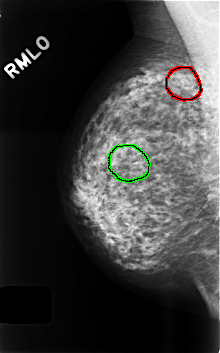

FILE: C_0497_1.RIGHT_MLO.OVERLAY

TOTAL_ABNORMALITIES 2

ABNORMALITY 1

LESION_TYPE CALCIFICATION TYPE PLEOMORPHIC DISTRIBUTION CLUSTERED

ASSESSMENT 4

SUBTLETY 3

PATHOLOGY UNPROVEN

TOTAL_OUTLINES 1

BOUNDARY

ABNORMALITY 2

LESION_TYPE CALCIFICATION TYPE AMORPHOUS DISTRIBUTION CLUSTERED

SUBTLETY 2

PATHOLOGY BENIGN